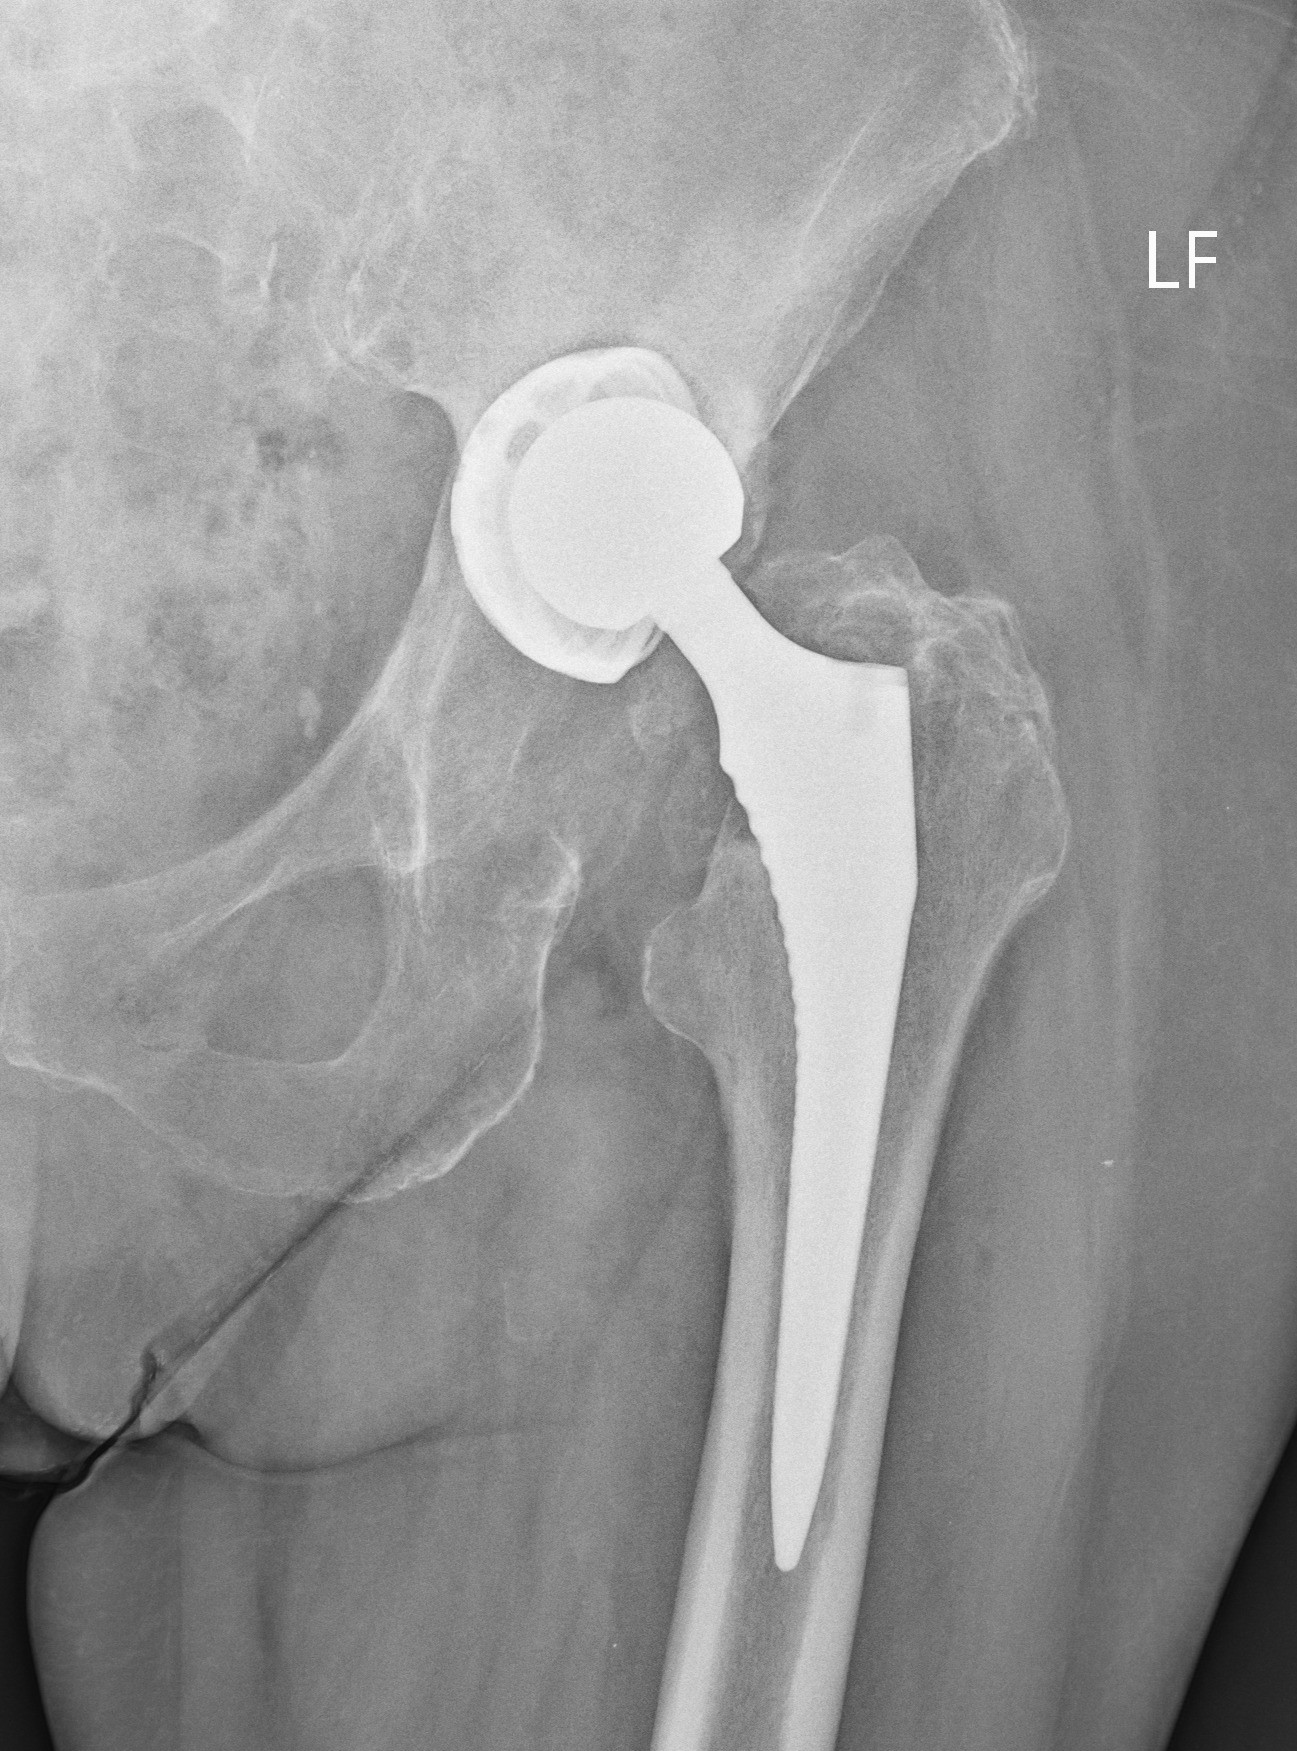

Tím II. ortopedicko – traumatologickej kliniky LF UK a UNB v Nemocnici sv. Cyrila a Metoda v Petržalke, pod vedením prednostu prof. MUDr. Borisa Šteňa, PhD. uskutočnil inovatívnu operáciu, počas revízie totálnej endoprotézy bedrového kĺbu. Inovácia spočíva v implantácii revízneho modulárneho komponentu.

Tento implantát novej generácie špeciálnych endoprotéz je určený pre operačnú liečbu zlyhaných endoprotéz pri rozsiahlych kostných defektoch. Išlo nielen o prvú operáciu na Slovensku, ale celkovo v poradí o štvrtú operáciu na svete s použitím tzv. „butress“ dlahy, vyrobenej z trabekulárneho titánu. Operácii sa úspešne podrobila 81 ročná pacientka s rozsiahlym kostným defektom v oblasti po implantácii jamky totálnej endoprotézy.

„S potešením môžem skonštatovať, že nám na pracovisku pri operačnej liečbe zlyhania totálnych umelých náhrad bedrových kĺbov pribudol inovatívny implantát. Máme tak k dispozícii viac možností na ošetrenie komplexných kostných defektov. Na rozdiel od predošlých implantátov, tieto vieme kombinovať ako čisto necementované alebo v kombinácii s kostným cementom a kostnými štepmi.“ uviedol Boris Šteňo, prednosta II. ortopedicko – traumatologickej kliniky LF UK a UNB. Rekonštrukcia veľkého kostného defektu na strane acetábula, teda v mieste implantácie jamky totálnej endoprotézy, býva vždy zložitá, niekedy žiaľ aj nemožná. Od tohto nového implantátu si naši odborníci sľubujú rozšírenie možnosti bezpečného použitia v revíznej endoprotetike, prípadne aj u pacientov po rozsiahlych kostných defektoch po zlomeninách panvy a acetábula.